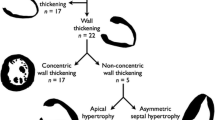

Myocardial crypts (defined as >50% penetration) were identified in 64 out of 1020 patients (6.3%) (Table 2). The inter-observer agreement in identifying crypts that fulfilled the 50% criteria was very strong (K = 0.92). 62 of the crypts are presented in Figure 1.

Age and gender were not significantly different between the group with and without crypts. Myocardial crypts were found significantly less frequently in our ‘control’ group compared to the overall cohort (3.6% vs 6.3%, p < 0.031). They were found more frequently in the phenotypic HCM group (9/76, 12%, p < 0.044) and in the hypertensive CM group (3/11, 27%, p < 0.025), where they were all located in segment 4. The prevalence of crypts in the other NICM or ICM groups was not statistically different (Figure 2).

Crypts were also found more commonly in the phenotypic normal group referred for screening based on a FH of inherited cardiomyopathy (10/41, 23%, p < 0.001) compared to the overall group. Including the small subgroup of 9 patients referred with a 1st degree relative with a clinical HCM diagnosis (3/9, 33%, p < 0.014) (Figure 2), again these were all located in segment 4 (AVI videos of these are included as on-line Additional files 1, 2, and 3). Of note, the only patient with a known disease-causing mutation did not have a myocardial crypt.

Multiple crypts were found in 11 patients (1.1%). These were mainly in the NICM group (7/374, 1.8%, p = 0.1), but this was not statistically significant compared to the overall group. For the purpose of further analysis where more than 2 crypts were identified, only the most prominent 2 were analyzed. By far the most common location for myocardial crypts was in the basal inferior segments (segment 4 – 52/ 75 (69%), other inferior segments 9/75 (12%), non-inferior segments 14/75 (19%). U shaped crypts (36/75) and V shaped crypts (28/75) were the most common appearance (i shaped 11/75).